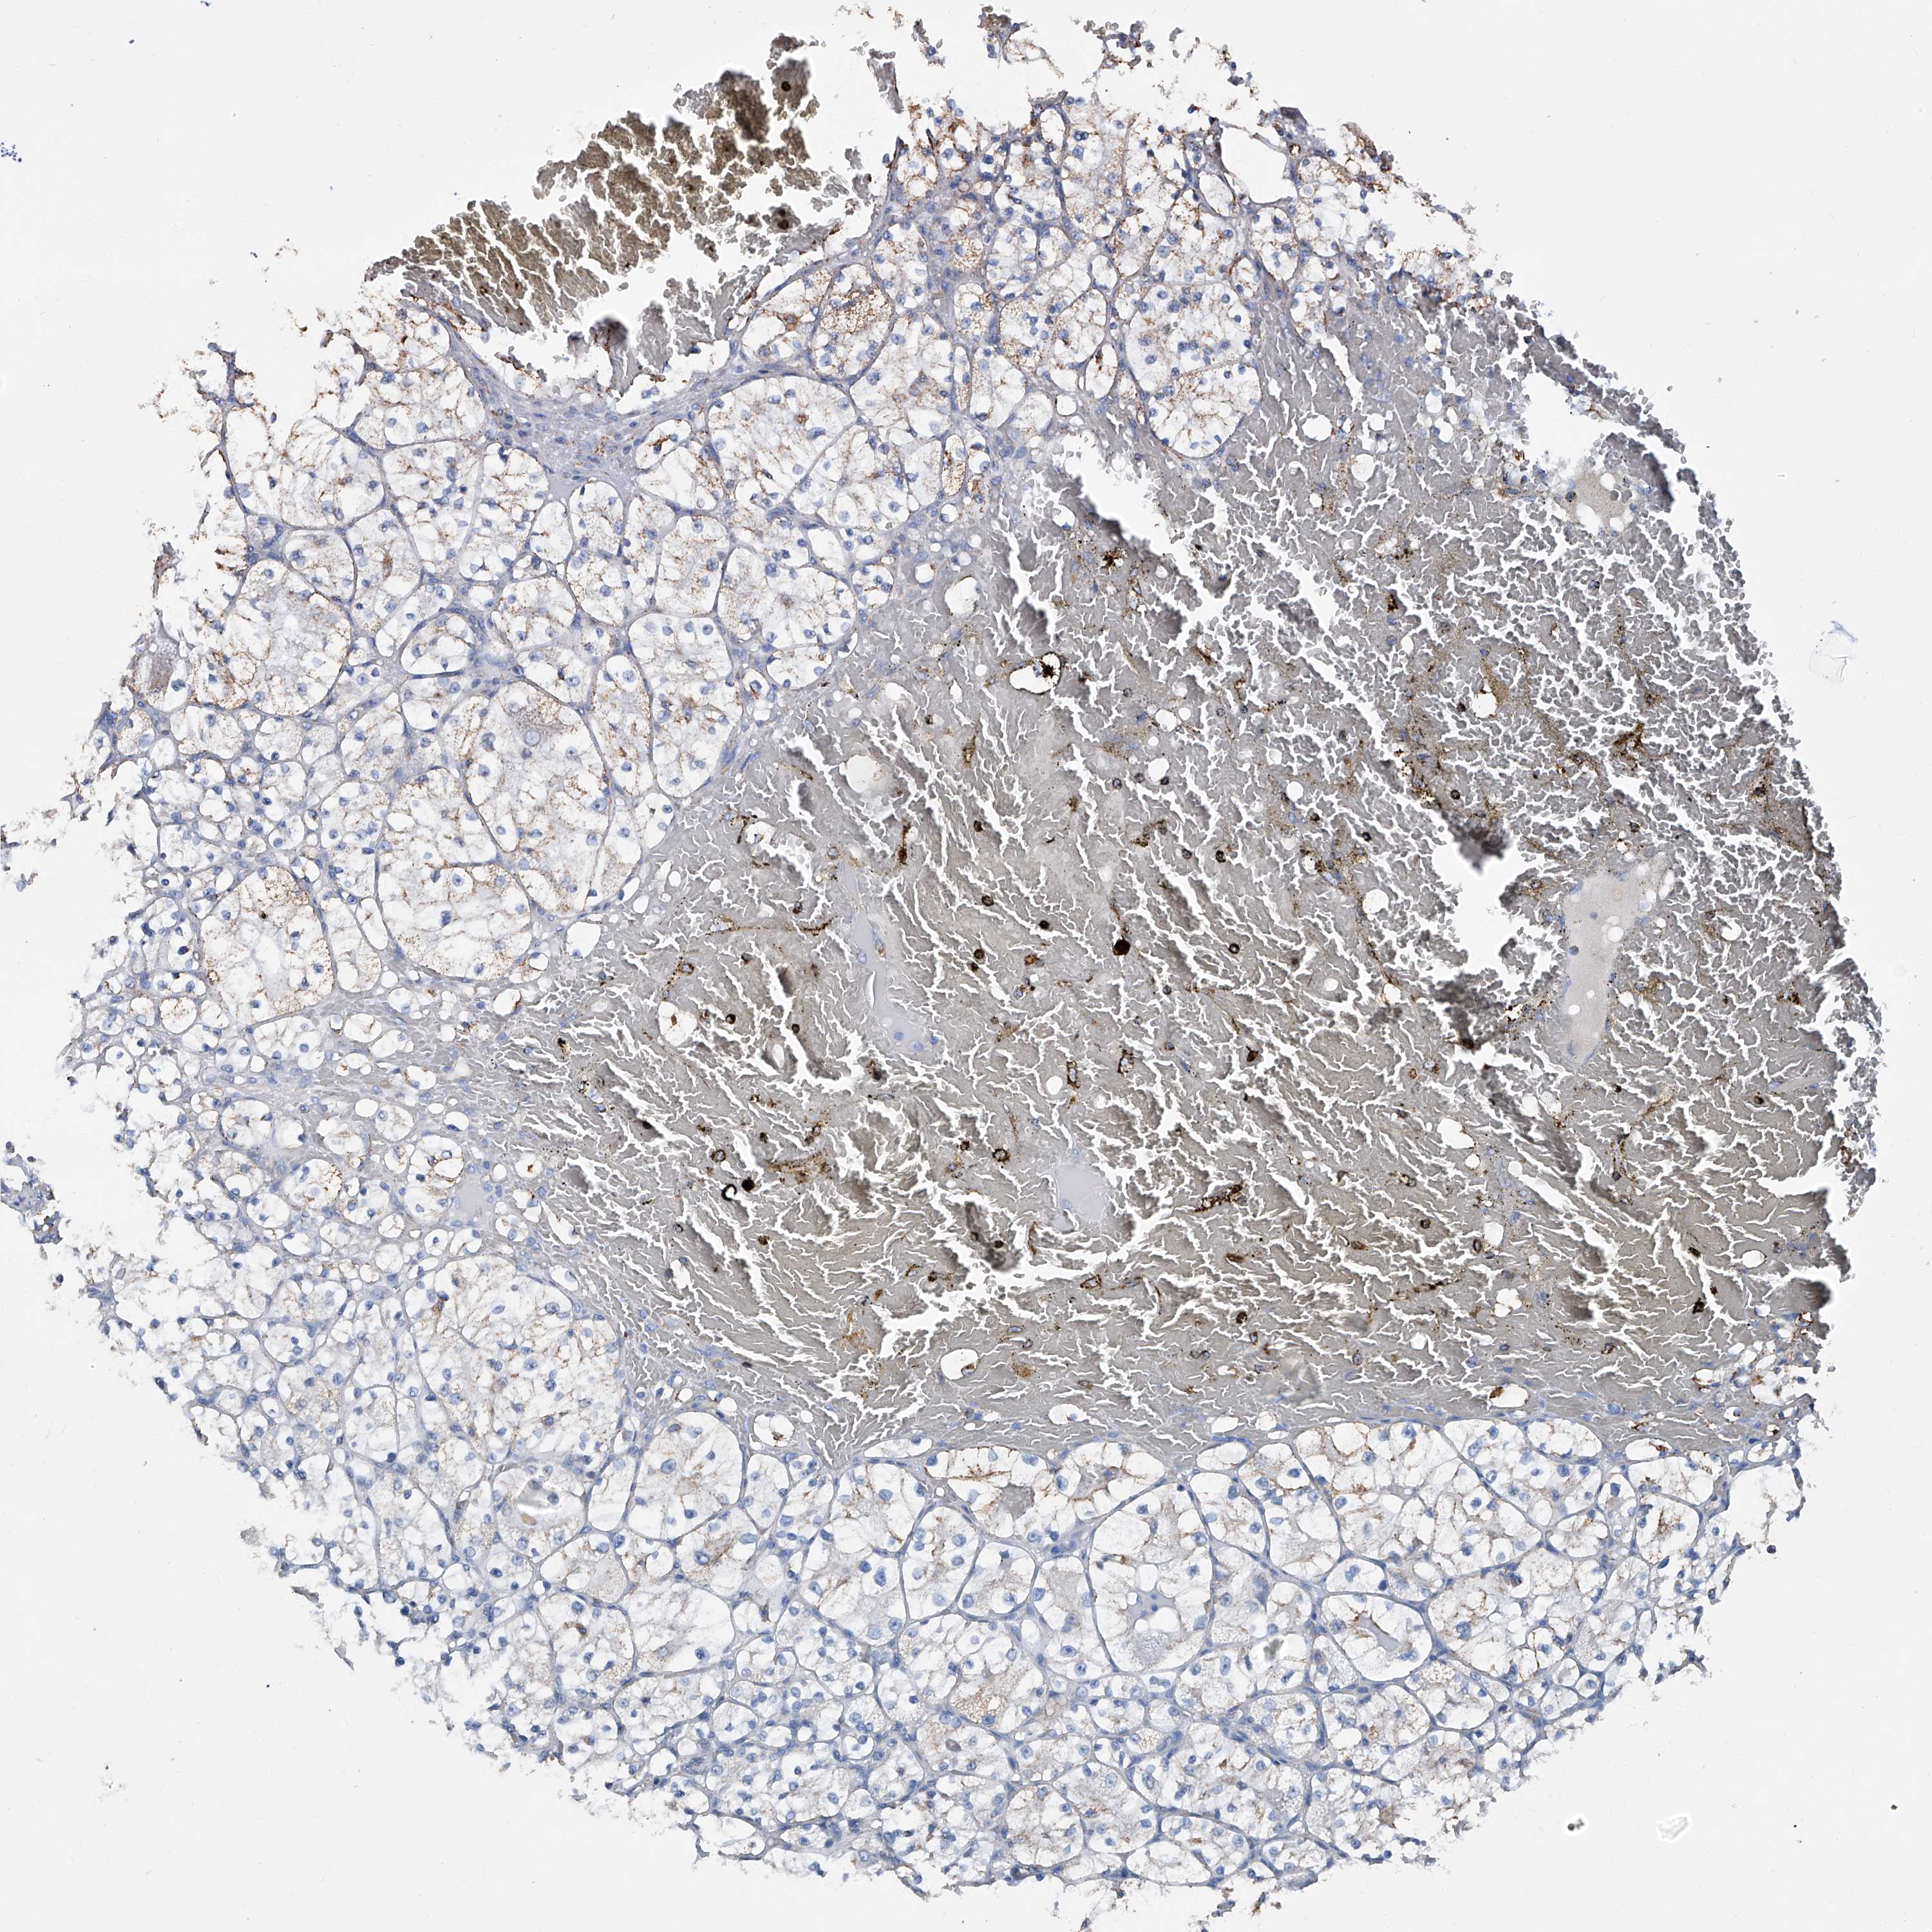

KIDNEY RENAL CLEAR CELL CARCINOMA (VALIDATION) - Interactive survival scatter ploti

The Survival Scatter plot shows the clinical status (i.e. dead or alive) for all individuals in the patient cohort, based on the same data that underlies the corresponding Kaplan-Meier plots. Patients that are alive at last time for follow-up are shown in blue and patients who have died during the study are shown in red.

The x-axis shows the expression levels (FPKM) of the investigated gene in the tumor tissue at the time of diagnosis. The y-axis shows the follow-up time after diagnosis (years). Both axes are complimented with kernel density curves demonstrating the data density over the axes. The top density plot shows the expression levels (FPKM) distribution among dead (red) and alive patients (blue). The right density plot shows the data density of the survived years of dead patients with high and low expression levels respectively, stratified using the cutoff indicated by the vertical dashed line through the Survival Scatter plot. This cutoff is automatically defined based on the FPKM cutoff that minimizes the p-score. The cutoff can be changed by dragging the vertical line or by entering a cutoff value in the square labeled "Current cut-off".

Under the Survival Scatter plot the p-score landscape (black curve; left axis) is shown together with dead median separation (red curve; right axis). Dead median separation is the difference in median mRNA expression between patients who have died with high and low expression, respectively. It is calculated as follows: median FPKM expression of dead patients with high expression - median FPKM expression of dead patients with low expression. This is intended to aid the user in visually exploring custom cutoffs and the associated p-scores and dead median separation.

Individual patient data is displayed and can be filtered by clicking on one or more of the category buttons on the top of the page. Categories describing expression level and patient information include: high, low, alive, dead, female, male and tumor stages. The scale of the x-axis can be toggled between linear and log-scale by clicking on the "x log" button. Mouse-over function shows TCGA ID, patient information and mRNA expression (FPKM) for each patient.

& Survival analysisi

Kaplan-Meier plots summarize results from analysis of correlation between mRNA expression level and patient survival. Patients were divided based on level of expression into one of the two groups "low" (under cut off) or "high" (over cut off). X-axis shows time for survival (years) and y-axis shows the probability of survival, where 1.0 corresponds to 100 percent.

NHS is not prognostic in Kidney Renal Clear Cell Carcinoma (validation)

Best expression cut offi

Based on the FPKM value of each gene, patients were classified into two groups and association between prognosis (survival) and gene expression (FPKM) was examined. The best expression cut-off refers the FPKM value that yields maximal difference with regard to survival between the two groups at the lowest log-rank P-value. Best expression cut-off was selected based on survival analysis .

When clicking on this number, the vertical dashed line indicating cut-off, the interactive survival plot, and the Kaplan-Meier curve will be adjusted to show results based on the best expression cut-off.

: 6.65

P scorei

Log-rank P value for Kaplan-Meier plot showing results from analysis of correlation between mRNA expression level and patient survival.

N/A

5-year survival highi

5-year survival for patients with higher expression than the expression cutoff.

For melanoma and glioma, 3-year survival is shown.

5-year survival lowi

5-year survival for patients with lower expression than the expression cutoff.

TCGA RNA samplesi

RNA-seq data is reported as average FPKM (number Fragments Per Kilobase of exon per Million reads), generated by the The Cancer Genome Atlas (TCGA) .

Normal distribution across the dataset is visualized with box plots, shown as median and 25th and 75th percentiles. Points are displayed as outliers if they are above or below 1.5 times the interquartile range. FPKM values of the individual samples are presented next to the box plot.

Average pTPM 6.1

Number of samples 100